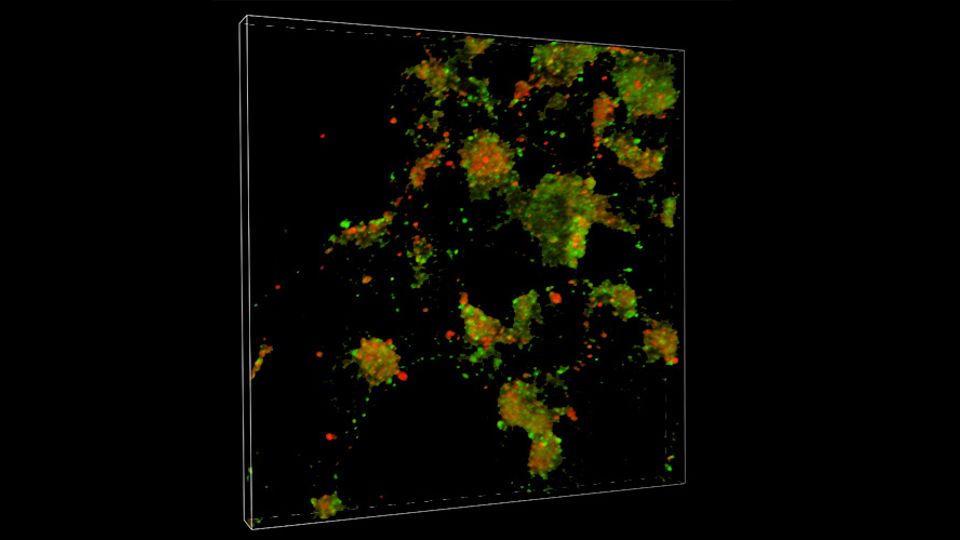

A team at Scripps Research reveals details into how Parkinson’s disease and Lewy body dementia spread in the brain. In neurons, the LC3 protein (green) and LAMP1 protein (red) fuse together into autolysomes (yellow) where autophagy, a cellular mechanism for clearing misfolded proteins, occurs. The prominence of green shows that autophagy has been blocked at the fusion step, allowing misfolded proteins like alpha-synuclein to instead spread throughout the brain. Credit: Scripps Institute

The p62 protein normally assists in autophagy, a waste-management system that helps cells get rid of potentially harmful protein aggregates. The researchers found evidence that in cell and animal models of Parkinson’s, p62 is S-nitrosylated at abnormally high levels in affected neurons. This alteration of p62 inhibits autophagy, causing a buildup of alpha-synuclein aggregates. The buildup of aggregates, in turn, leads to the secretion of the aggregates by affected neurons, and some of these aggregates are taken up by nearby neurons.